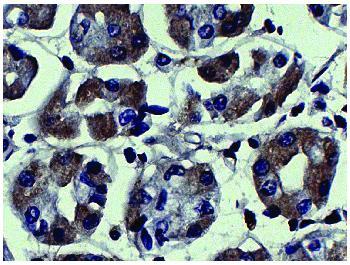

Figure 1: Human kidney cancer tissue was stained with Mouse Anti-Human MMP-3 followed by Goat Anti-Mouse IgG2a, Human ads-HRP .